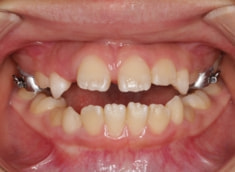

治療後(1年5ヶ月後)